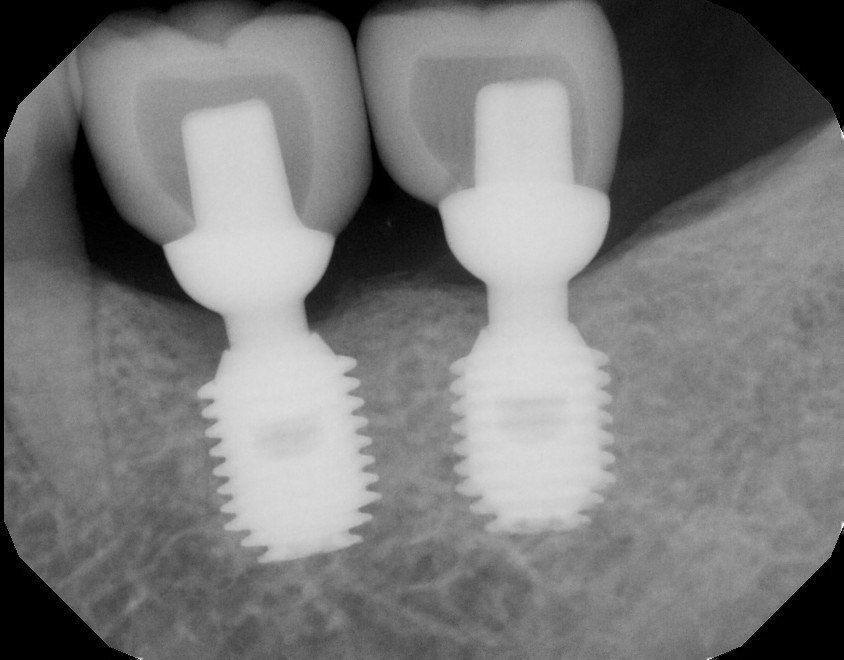

Dental Implants

Our implant specialists use state-of-the-art technology to place titanium posts that act as artificial tooth roots, providing a strong foundation for replacement teeth. This treatment not only restores your smile but also helps maintain your jaw bone structure and facial contours.